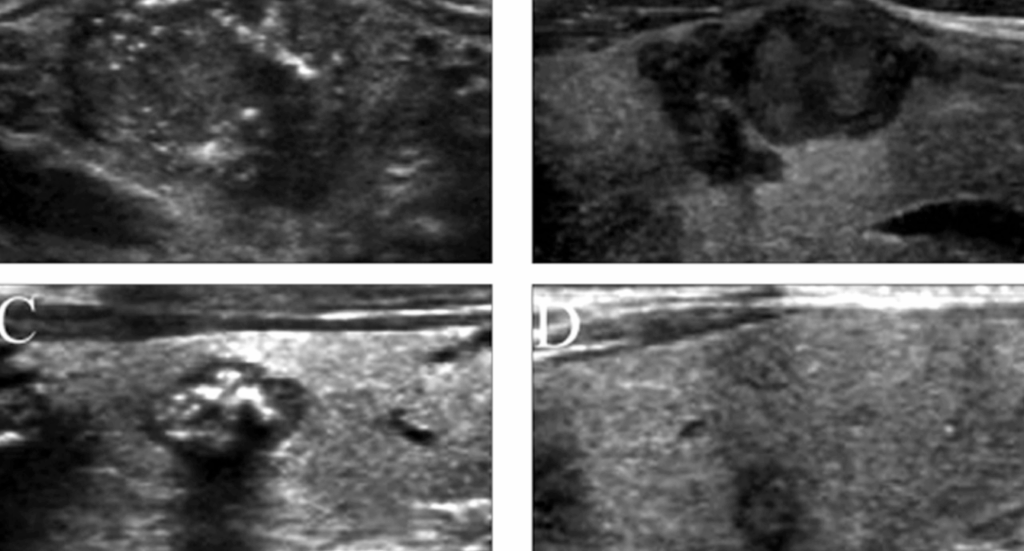

Ultrasound is the primary imaging modality for evaluating thyroid nodules. In medullary thyroid cancer, ultrasound may reveal a hypoechoic nodule with irregular borders, increased vascularity, and the presence of microcalcifications. These microcalcifications appear as tiny, bright echogenic spots without acoustic shadowing, distinguishing them from coarse calcifications seen in benign conditions.

The detection of microcalcifications on ultrasound is significant, as it guides the decision to perform an FNA biopsy. Moreover, ultrasound assists in assessing cervical lymph nodes for metastatic involvement, which is common in MTC. Features such as rounded lymph nodes with loss of the fatty hilum and microcalcifications within the nodes suggest metastatic disease, influencing surgical planning and prognosis.

Microcalcifications are tiny calcium deposits that appear as punctate echogenic foci on ultrasound imaging. In the context of thyroid nodules, their presence is considered a suspicious feature, often associated with malignancy. These calcifications are thought to result from psammoma bodies or necrotic debris within the tumor. In medullary thyroid cancer, microcalcifications are observed in approximately 52% of cases, serving as a critical sonographic marker that raises the index of suspicion for malignancy.

The identification of microcalcifications on ultrasound necessitates further evaluation, typically through fine-needle aspiration (FNA) biopsy. Their presence, especially when combined with other suspicious features like hypoechogenicity and irregular margins, significantly increases the likelihood of a malignant diagnosis. Therefore, recognizing microcalcifications is vital in the early detection and management of MTC.